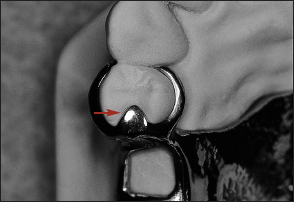

Unlike extracoronal retainers, intracoronal retainers are contained entirely within the contours of a clinical crown (Fig 1-4). Consequently, the use of intracoronal retainers generally requires the fabrication of two or more specially designed, complete-coverage crowns. In most instances, retention of intracoronal removable partial dentures is dependent upon exact parallelism of the retentive assemblies. Each assembly consists of two parts, commonly termed matrix (“female”) and patrix (“male”). Figure 1-5 illustrates the joining of a patrix and matrix to form a functional retentive unit. When a dislodging force is applied to the removable partial denture, binding occurs between the external walls of the patrix and the internal walls of the matrix. This binding results in retention of the prosthesis.

Fig 1-5 When joined, matrix and patrix components form a closely fitting retentive assembly.